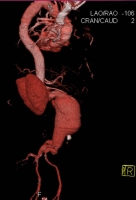

En el ejemplo de película se trata de un AAA infrarrenal cerrado con un diámetro de > 5 cm: